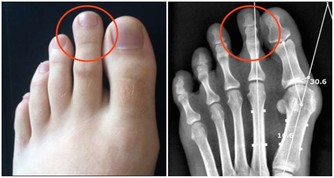

二是口源性口臭:這是最常見的,像齲齒、牙周病、阻生齒,牙縫裡的食物殘渣等等,都會導致它出現,去看牙醫就能治好。